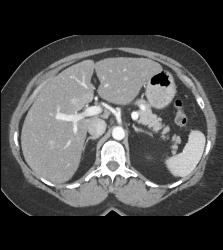

Splenule in Splenic Hilum